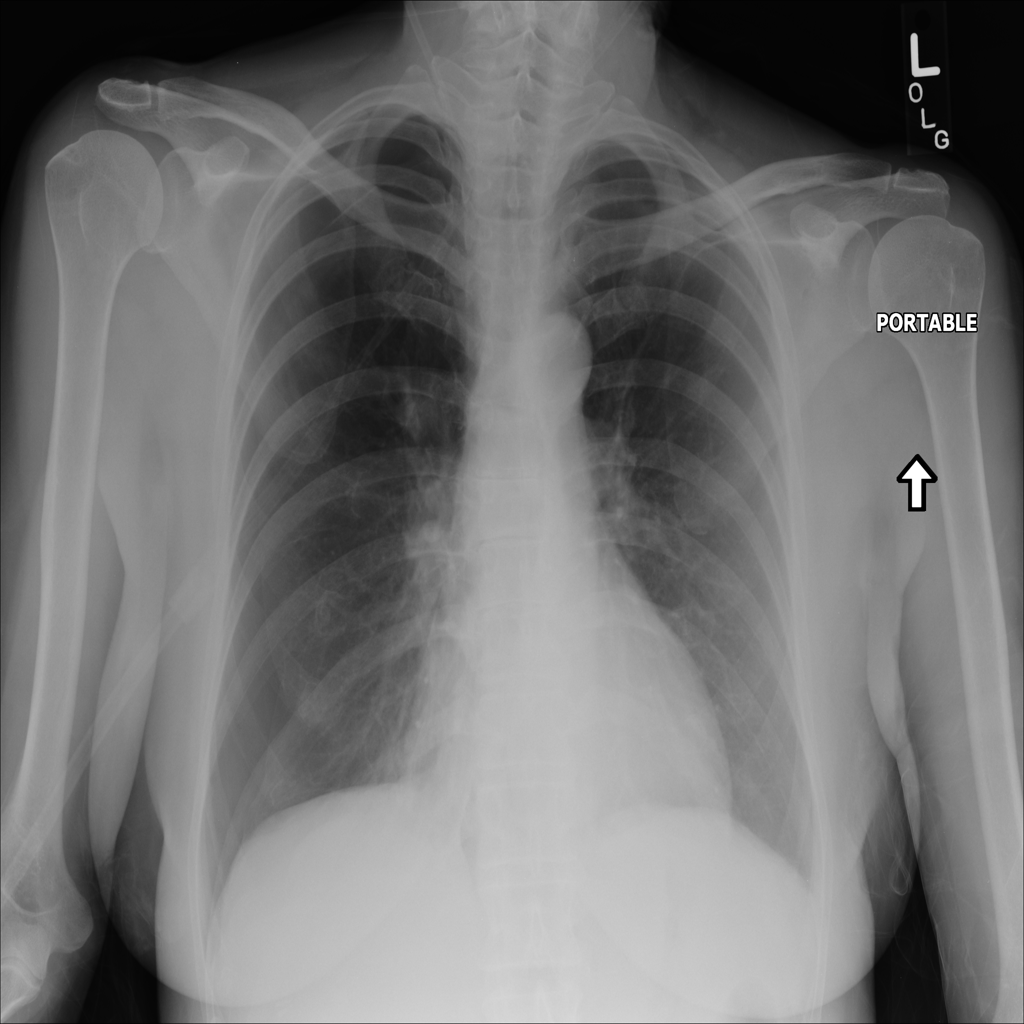

PAT-4639 · IMG-011Pneumothorax

PAT-4639 · IMG-011

AP